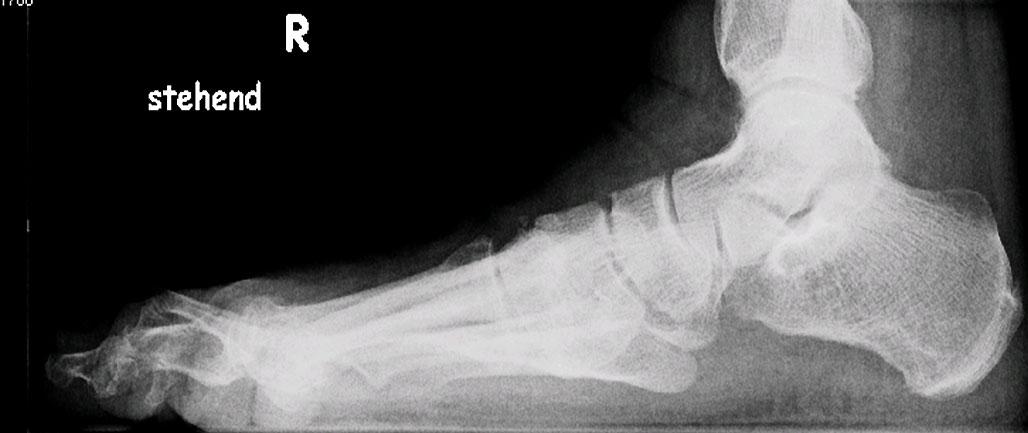

Im seitlichen Röntgenbild werden dorsale Osteophyten des Großzehengrundgelenkes als Ausdruck arthrotischer Veränderungen des Grundgelenkes befundet, eine nach dorsal gewinkelte Stellung der Oberkante des Metatarsale I im Verhältnis zum Metatarsale II deutet auf eine Elevatusposition des 1. Strahles hin (Abb. 7). Gelegentlich kann im seitlichen Röntgenbild ein plantares Klaffen des TMT I als Ausdruck einer Instabilität zu sehen sein (Abb. 8). Parallel verlaufende Metatarsalia I und II sind jedoch keinesfalls ein sicherer Beweis für das Fehlen einer Insuffizienz des 1. Strahles, da die Stellung der beiden Metatarsalia zueinander durch Rückfuß-Valgusdeformitäten fehlprojiziert sein kann.